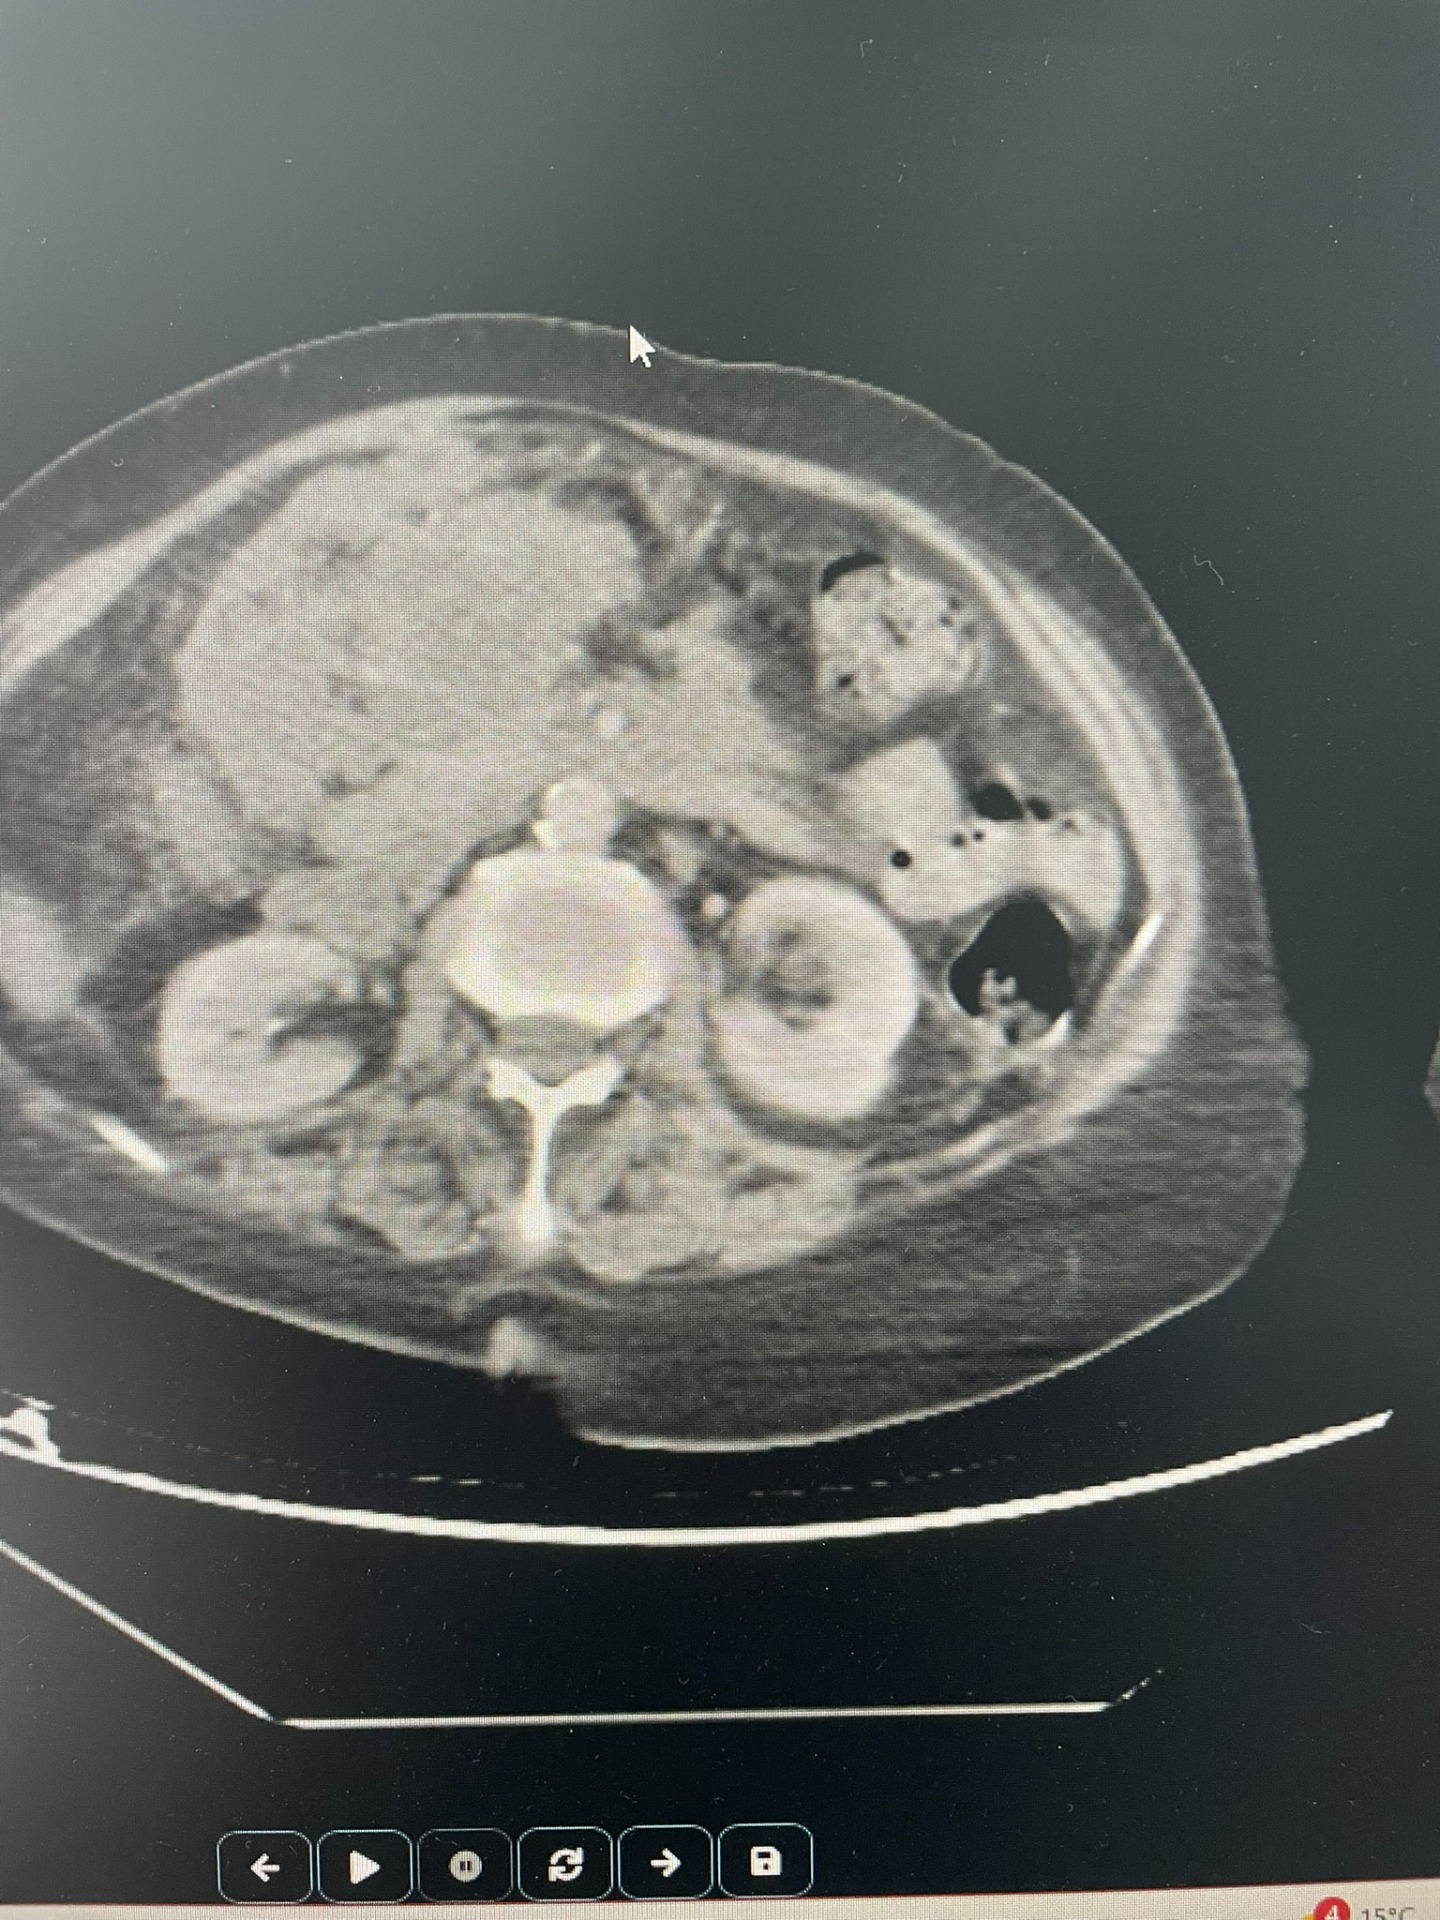

Renal renkli Doppler ultrason, böbreklerin yapısını ve özellikle böbrek damarlarındaki kan akımını değerlendiren, radyasyon içermeyen güvenli bir görüntüleme yöntemidir.